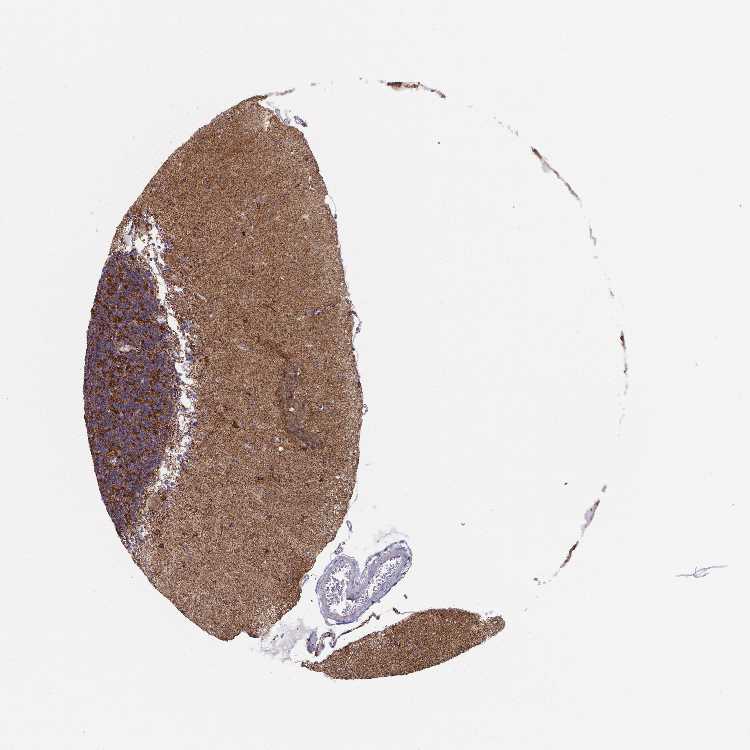

CEREBELLUM - Antibody stainingi

Antibody staining in the annotated cell types in the current human tissue is reported as not detected, low, medium, or high, based on conventional immunohistochemistry profiling in selected tissues. This score is based on the combination of the staining intensity and fraction of stained cells.

Each image is clickable and will lead to virtual microscopy that enables deeper exploration of all samples and also displays staining intensity scores, fraction scores and subcellular localization as well as patient and tissue information for each sample.

Antibody HPA043922Antibody CAB033742

Purkinje cells MediumHigh

Cells in granular layer HighHigh

Cells in molecular layer HighMedium